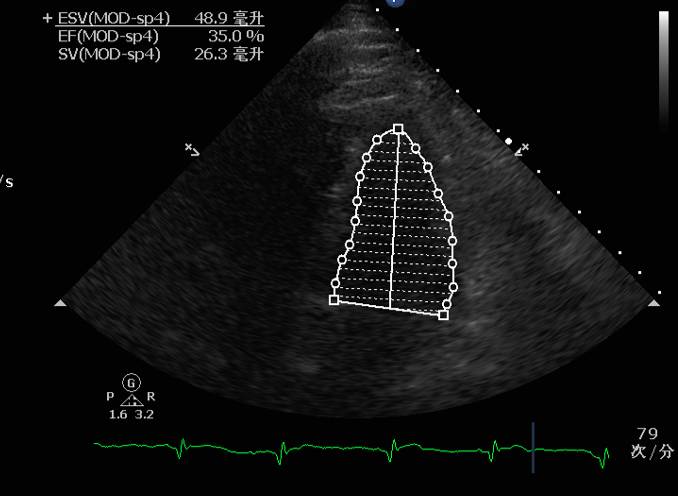

EF:0.35

♥床边心超提示:心率增快时左心收缩力明显减弱,伴充盈压高,予以艾司洛尔(0.05mg/kg/min)控制心室率后心率降至55左右,血压明显改善,102/70mmHg,复查心超左心收缩舒张功能均改善。

♥心脏舒缩功能好转,循环灌注改善(无酸中毒,乳酸正常)